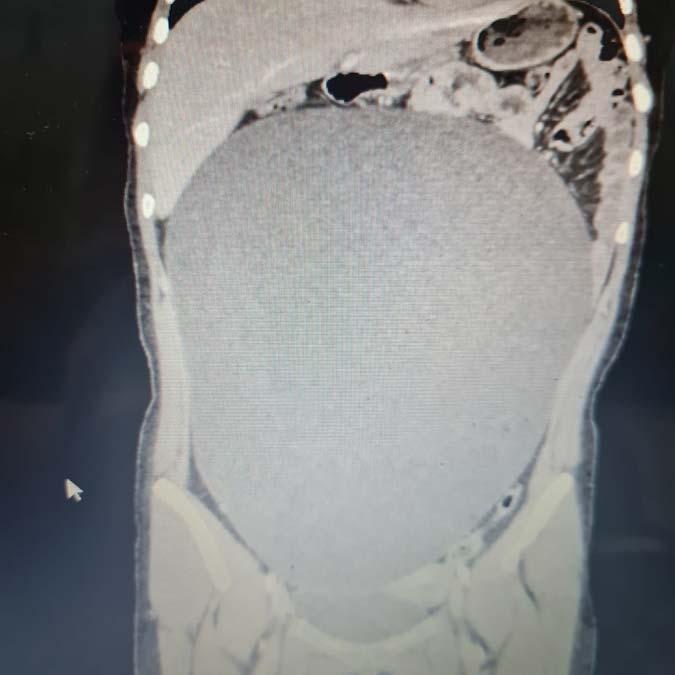

Kaza, 25 Ağustos günü saat 18.30 sıralarında Taşpazar Mahallesi Atatürk Bulvarı’nda meydana geldi. Üniversiteye hazırlık kursundan çıkan B.G., yolun karşısına geçmek isterken halk otobüsü çarptı. Kazada yaralanan B.G., çağrılan ambulansla Aksaray Eğitim ve Araştırma Hastanesi’ne kaldırıldı. Tetkikler sırasında B.G.’nin karnında kitle tespit edildi. Ameliyata alınan B.G.’nin karnından 60 santimetre büyüklüğünde, 7 kilo 800 gram kitle çıkarıldı.

Ameliyatı gerçekleştiren Dr. Ayşe Betül Öztürk ise B.G.’nin karnındaki kitlenin doğuştan olduğunu ve giderek büyümesine rağmen hasta ve yakınları tarafından fark edilmediğini belirtti. Kaza vakası sonrası böyle bir olayı ilk kez yaşadıklarını belirten Öztürk, ”Kızımız, bir trafik kazısı geçiriyor ve kendisine otobüs çarpması sonrası acil servise getiriyor. Rutin kontrolleri yapılırken çekilen tomografisinde karın içerisinde büyük bir kitle olduğunu tespit edildi. Neredeyse bütün karnını kaplayan bir kitle nedeniyle hastayı hemen ameliyat aldık.

Başarı bir ameliyatla yaklaşık 60 santimetre büyüklüğünde ve 7 kilo 800 gram ağırlığındaki kitleyi hiçbir sorun yaşamadan çıkardık. Hastamızın şu an da durumu iyi ve besleniyor. Daha önce 26 santimetrelik bir kitle görmüştüm. Bu ise ondan daha büyük ve bütün karnını kaplamış şekilde, bütün organları itilmiş ve yer değiştirip küçülmüş ve yetirince gelişmemişti. Şu anda karın içinde ciddi bir boşluk oluştu. Kızımız da 7 kilo vermiş oldu. Bu kitle aslında doğuştan varmış ve giderek yavaş yavaş büyümüş. Fark edilmemesinin nedeni ise hiç ağrı yapmamış olması.